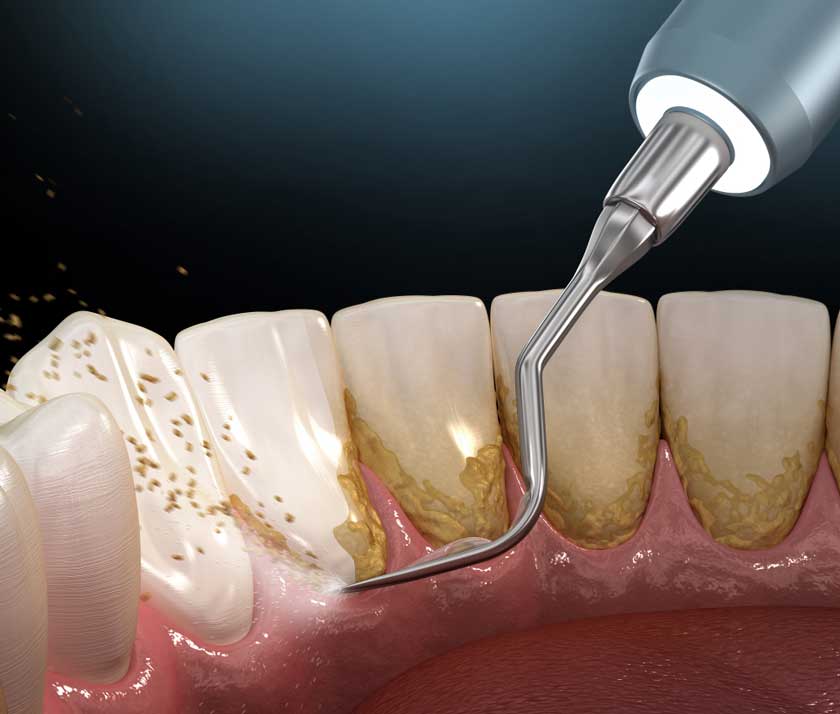

Vì vôi răng cứng và bám chặt, nên việc đánh răng thông thường không thể loại bỏ vôi răng mà cần đến các dụng cụ chuyên dụng tại nha khoa.

Với dịch vụ cạo vôi răng, Khách hàng sẽ được ứng dụng công nghệ cạo vôi răng bằng sóng siêu âm, hoàn toàn không gây đau hay khó chịu khi thực hiện, đặc biệt không ảnh hưởng đến răng nướu và không để lại biến chứng.